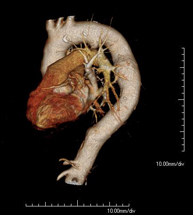

- Thoracic aorta CT angiography

Diagnostic test to examine the thoracic aorta (main artery of the thorax) using CT (Computed Tomography) equipment. This technique requires the use of an iodinated contrast agent, and provides high definition anatomical images. The use of MDCT (Multidetector Computed Tomography) shortens scanning time, reduces radiation dose and improves image quality. The multiple detectors used in certain studies enable imaging to be synchronised with the heartbeat, a technique used to study the aortic valve and aortic root (the first few centimetres), where the heartbeat often distorts images due to movement.